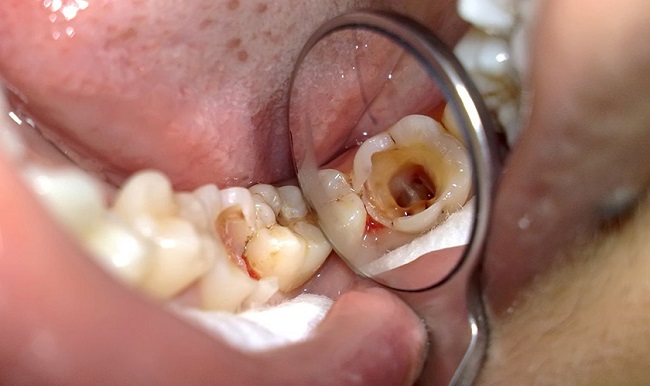

Sâu răng và viêm tủy

Sâu răng chính là nguyên nhân phổ biến nhất gây ê buốt răng, đặc biệt khi tiến triển nặng, phá hủy cấu trúc phần men và ngà răng. Các vi khuẩn trong khoang miệng sẽ sinh sôi, tạo ra axit phá vỡ men răng, hình thành các lỗ hổng, nơi dây thần kinh dễ bị kích thích khiến bạn cảm thấy đau nhói rõ rệt.

Khi sâu răng tiến sâu tới lớp tủy, các dây thần kinh trong tủy răng bị viêm hoặc kích thích, gây ra cảm giác ê buốt dữ dội kèm theo đau dữ dội, kéo dài. Lúc này, cần can thiệp y tế phòng tránh biến chứng nặng như nhiễm trùng hoặc mất răng. Đồng thời, các biện pháp tại nhà chỉ giúp giảm cảm giác tạm thời mà không thể chữa khỏi triệt để khi bệnh đã nặng.

Điều trị sâu răng hoặc viêm tủy răng là cách duy nhất đảm bảo triệt để tình trạng nhạy cảm này. Vì vậy, việc phát hiện sớm và chăm sóc đúng cách sẽ giúp bảo vệ chiếc răng của bạn tốt hơn, hạn chế tối đa việc phải thực hiện các phương pháp trám răng hay điều trị phức tạp về sau.